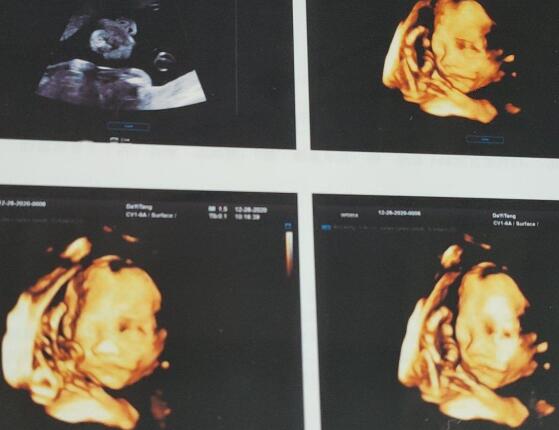

1、b超检查:孕妇在进行剖腹产前两个礼拜左右,还应及时进行相关的b超检查,以便及时了解胎位,剖腹产手术的顺利进行;

除了上述的这些术前检查以外,孕妇还可以做彩超检查,判断羊水量、胎儿体重、胎儿双顶径、胎盘功能以及子宫瘢痕厚度、胎盘位置等。同时也可以做宫颈检查,确定宫口扩张的情况以及宫颈的成熟度,只有这样才可以为生产做好各种准备。

4、B超检查:剖腹产手术之前需要先做腹部B超检查,能够观察胎儿的情况或者是羊水的情况,从而增加手术的成功率;